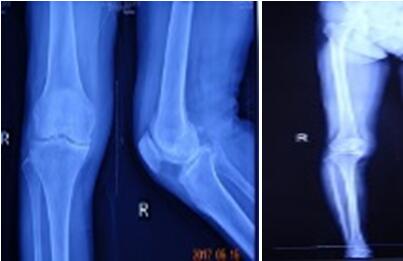

近日骨科在張富軍主任帶領(lǐng)下,在保膝理念的驅(qū)動(dòng)下,成功開展我院首例生物單髁膝關(guān)節(jié)置換術(shù),更是全國第9例,西北地區(qū)第2例。這意味著本次手術(shù)在西安市內(nèi)乃至整個(gè)西北地區(qū)都極為罕見,我院在骨關(guān)節(jié)病診治技術(shù)邁上了新的臺(tái)階,為膝關(guān)節(jié)炎患者提供了一種新的選擇。

提起膝關(guān)節(jié)置換術(shù),多數(shù)病人起初都是拒絕的,至少在單髁置換術(shù)出現(xiàn)之前,不乏有“談虎色變”的患者,而這些患者普遍遺留這樣一個(gè)問題:能否僅置換部分磨損的關(guān)節(jié),保留大部分自體關(guān)節(jié),用更小的創(chuàng)傷解決痛苦呢?答案是肯定的,隨著科技的進(jìn)步和手術(shù)技術(shù)的精湛,單髁關(guān)節(jié)置換應(yīng)運(yùn)而生,成為近2年風(fēng)靡一時(shí)的手術(shù)方式,術(shù)中要求精確至1mm,其具有創(chuàng)傷小,恢復(fù)快,骨長入理想,骨質(zhì)保留量大,本體感覺不破壞的優(yōu)勢。目前膝關(guān)節(jié)單髁置換多為骨水泥型,生物型全國僅開展9例。生物型作為全新的置換方式比骨水泥型更具有突出的優(yōu)勢,逐漸成為新的趨勢。